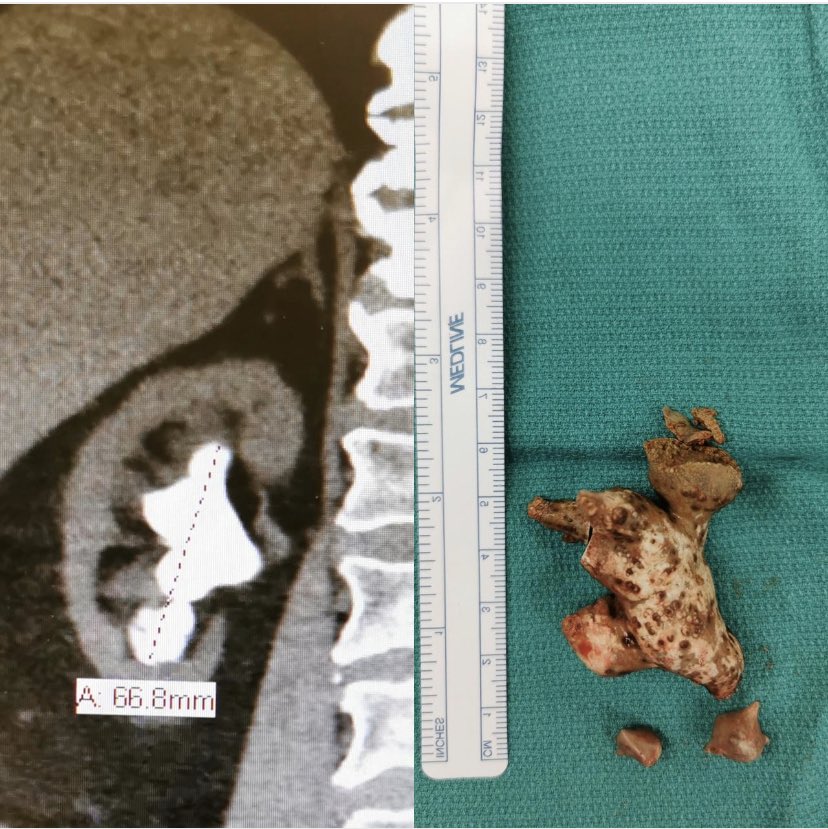

ちなみにギザギザに特化したやつもあるよ

no title

49: 以下、5ちゃんねるからVIPがお送りします 2020/11/27(金) 15:20:17.678 ID:EPtKEGLG0

>>38

3枚目が殺意しかなくて草

42: 以下、5ちゃんねるからVIPがお送りします 2020/11/27(金) 15:01:17.703

最後えげつない

44: 以下、5ちゃんねるからVIPがお送りします 2020/11/27(金) 15:05:51.898 ID:OZYMmDVCa

三枚目モーニングスターじゃん